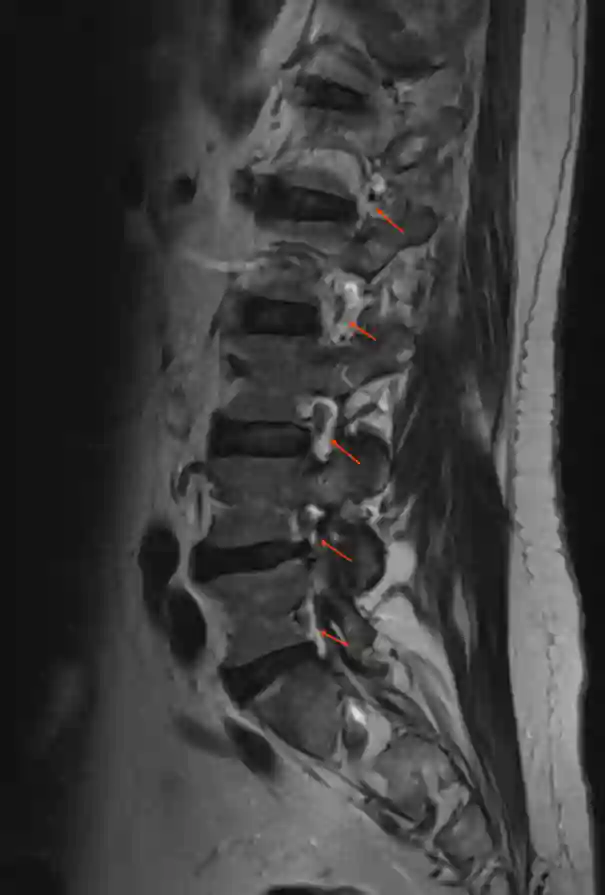

Foramen intervertebrale MRI

Sagittale T2 MRI Sequenz der Lendenwirbelsäule mit Darstellung der Foramina intervertebralia.